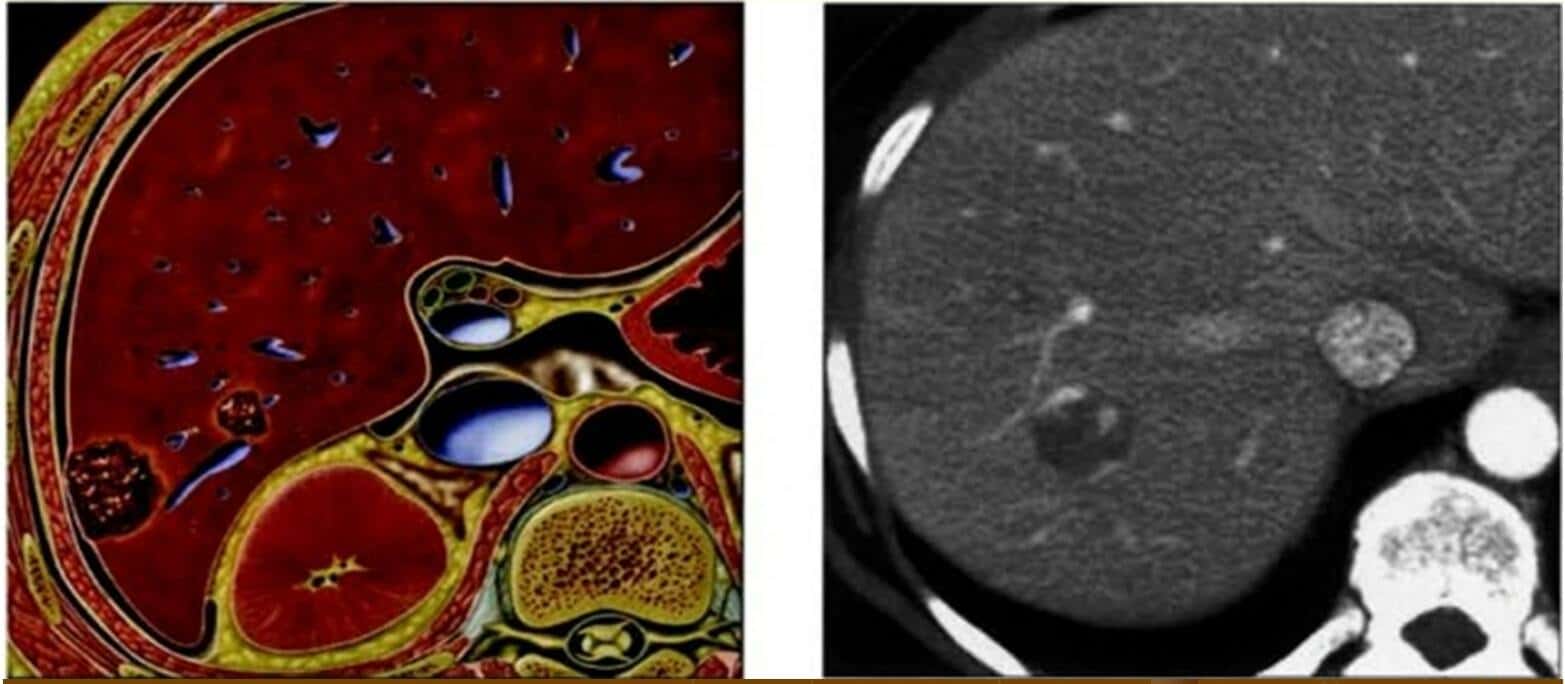

Ca lâm sàng » Tiêu Hóa » U máu gan [170 cases]

U máu gan [170 cases]

Danh mục: Tiêu Hóa